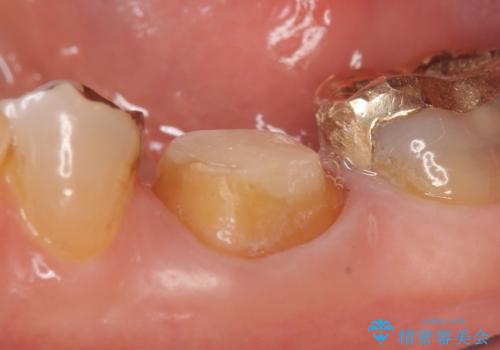

検査の結果左下6に根尖病変を認めたため、再根管治療を行いました。

その後症状の消失を確認し、オールセラミッククラウンによる補綴を行いました。